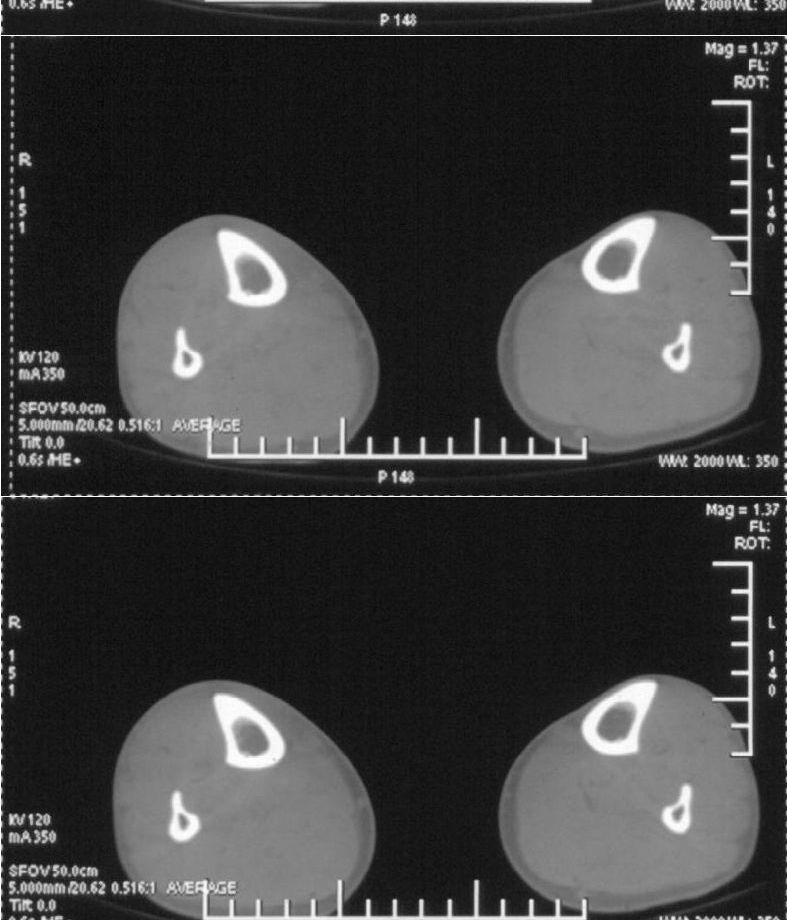

男,42岁。4个月前钢筋钝伤右侧小腿部,当时因无明显外伤,未引起重视。一周后因受伤腿部疼痛,发现肿胀,随后到当地医院进行检查(2008年4月16日)。因未发现骨质异常未引起重视,仅仅进行口服抗生素治疗处理。经过一段时间治疗但未见明显治疗效果在5月29日又进行x线检查,发现有胫骨密度上段密度增高,又进行抗炎治疗,仍未见效果。又在7月3日进行x线检查,仍然报告有胫骨上端密度增高,并建议ct检查。以下是相关检查结果:

髓腔密度呈絮状增高,胫骨上端内侧可见层状骨膜反应,考虑骨髓炎.

髓腔密度呈絮状增高,胫骨上端内侧可见层状骨膜反应,肌间隙模糊,考虑骨髓炎.